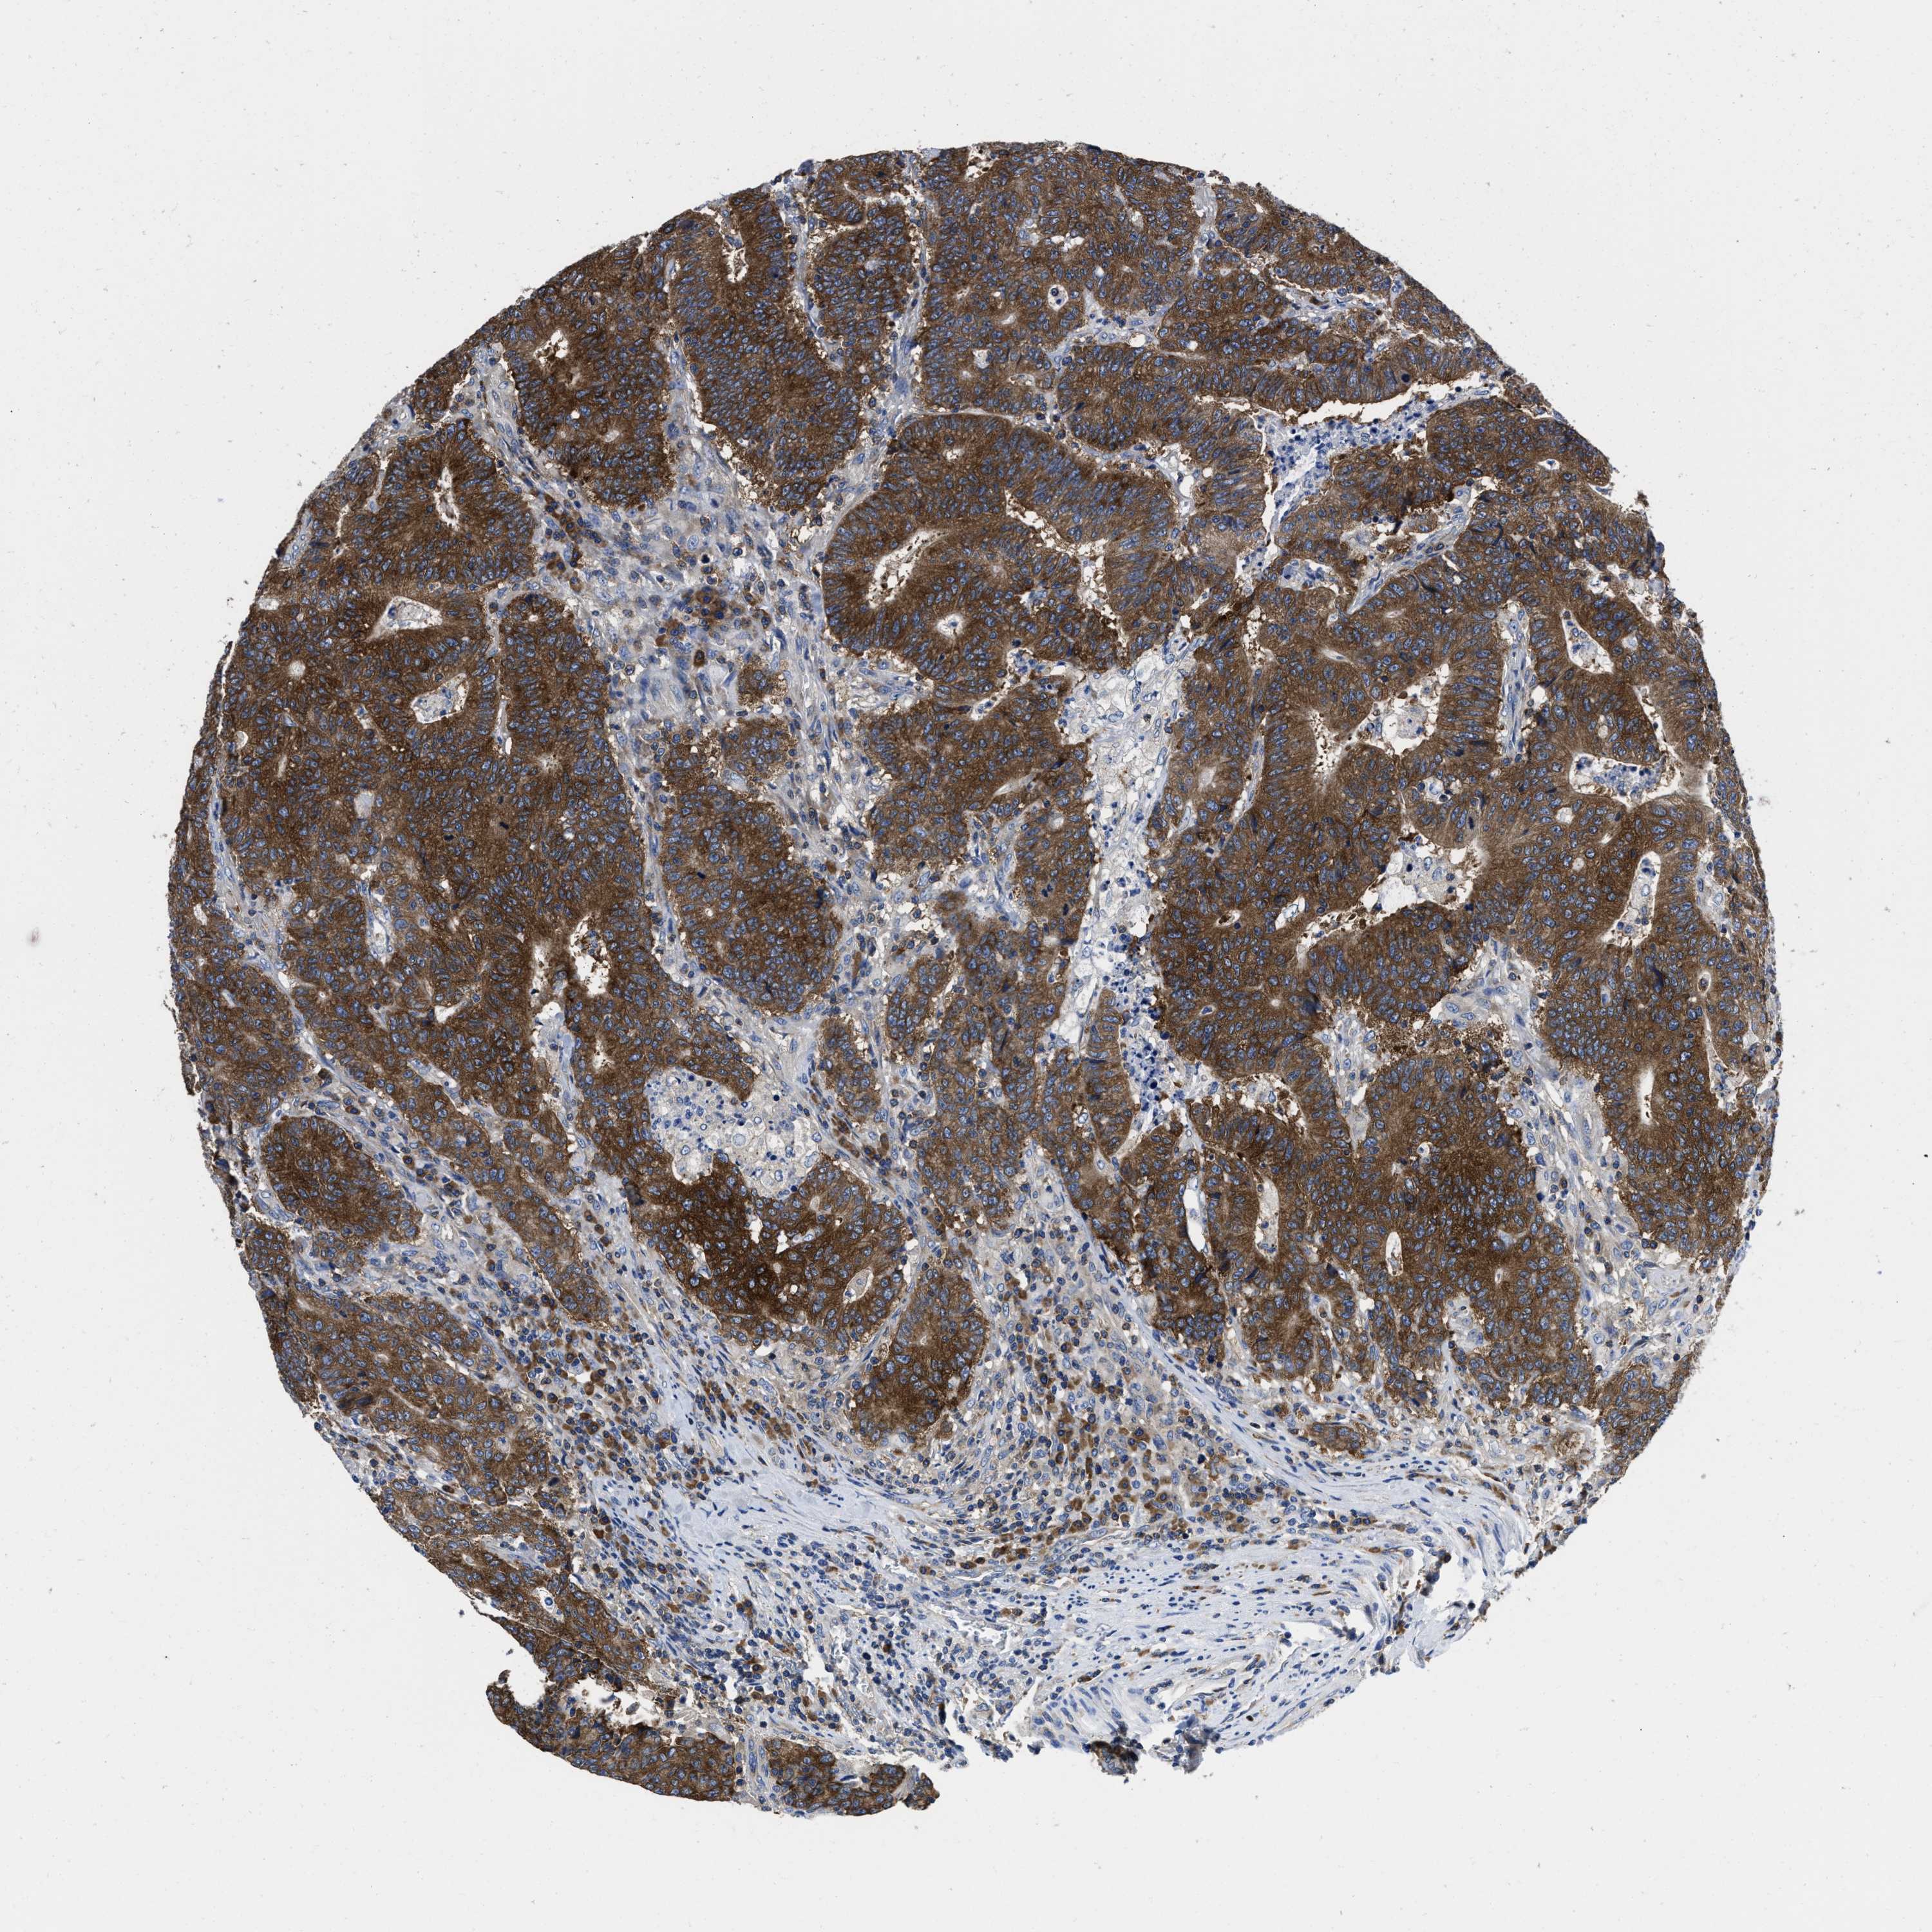

CANCER COLORECTAL CANCER Show tissue menu

Colorectal cancer

Colon adenocarcinoma